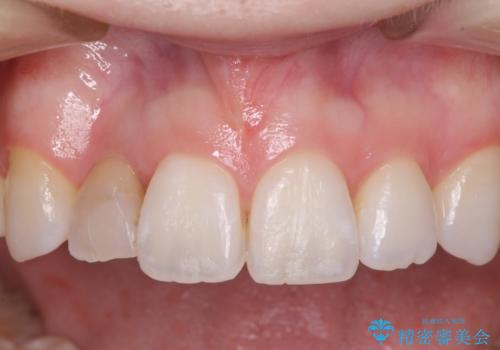

変色した前歯 オーダーメイドタイプのオールセラミッククラウン

- 虫歯により神経を取り除いた前歯の変色が気になるとのことで来院された患者様です。

レントゲン写真より、歯根の炎症が認められなかったため、ファイバーコアによる土台築製後、オーダーメイドタイプのオールセラミッククラウンにて補綴することとしました。

他院で矯正治療をされていたそうですが、矯正治療前から変色は気になっており、歯並びが整ってからは、より気になるようになっていたそうです。

自然に仕上がり、患者様には大変満足していただきました。